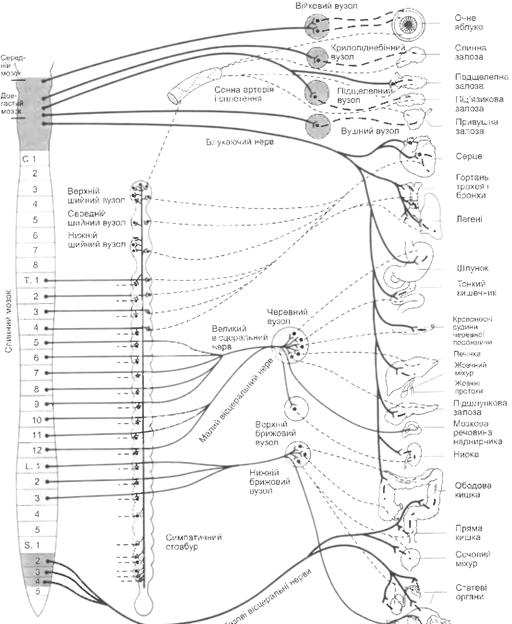

Регуляція вегетативної нервової системи

Фізіологія нервової системи

Реакція ефекторних органів на імпульси ВНС і циркулюючих катехоламінів